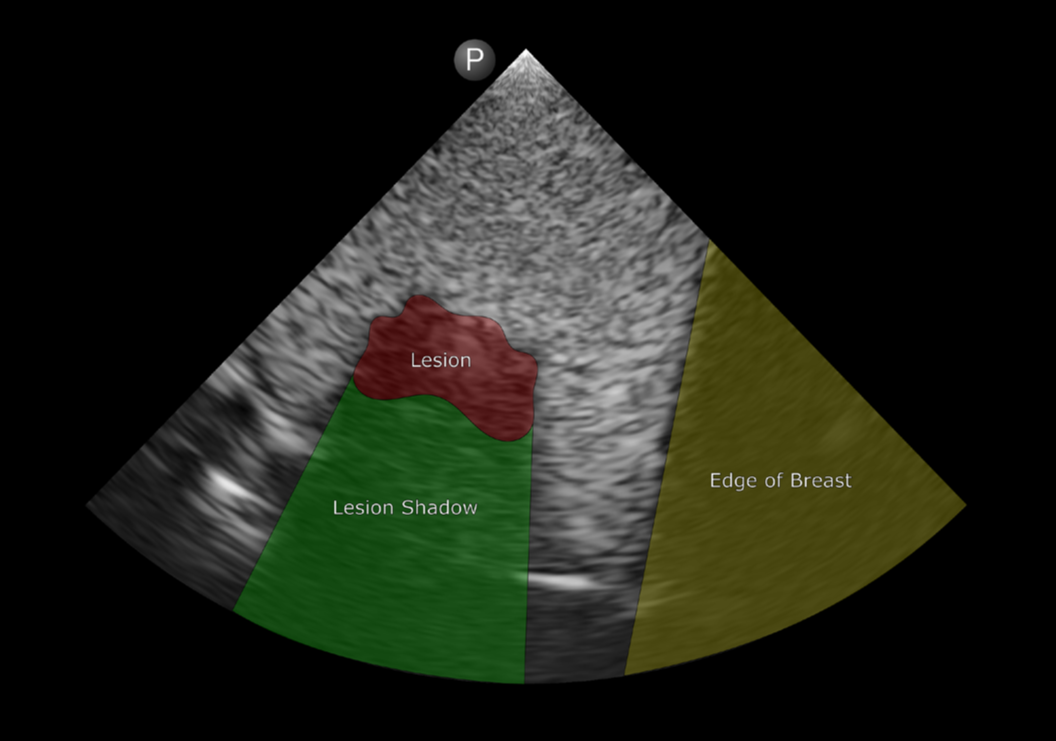

Digital Anatomyの材料と匿名化された患者のMRIスキャンを用いて、研究チームは超リアルな乳房組織モデルを作成することを目指しました。

GrabCAD Printソフトウェアの解剖学的プリセットライブラリから、彼らは乳房組織自体を再現するために「Encapsulated Subcutaneous Fat(封入皮下脂肪)」を、そして腫瘍には「Solid Internal Organ 6(固形内臓器官6)」を選択しました。

ポイントオブケア超音波(POCUS)を使うと、チームはすぐに病変を視覚化できましたが、より強力なプローブを備えた超音波検査室に移行した際、POCUSの設定に合わせるために周波数を下げる必要があることを発見しました。この調整により、プリントされたモデルが実際のヒト乳房組織からの信号と類似した信号を生成することが保証されました。

モデルのリアリティを高めるために、彼らは皮膚表面に「Soft DM 400」プリセットを施してモデルを仕上げました。これにより、効果的な超音波透過を可能にしつつ、生きているかのような感触が実現されました。